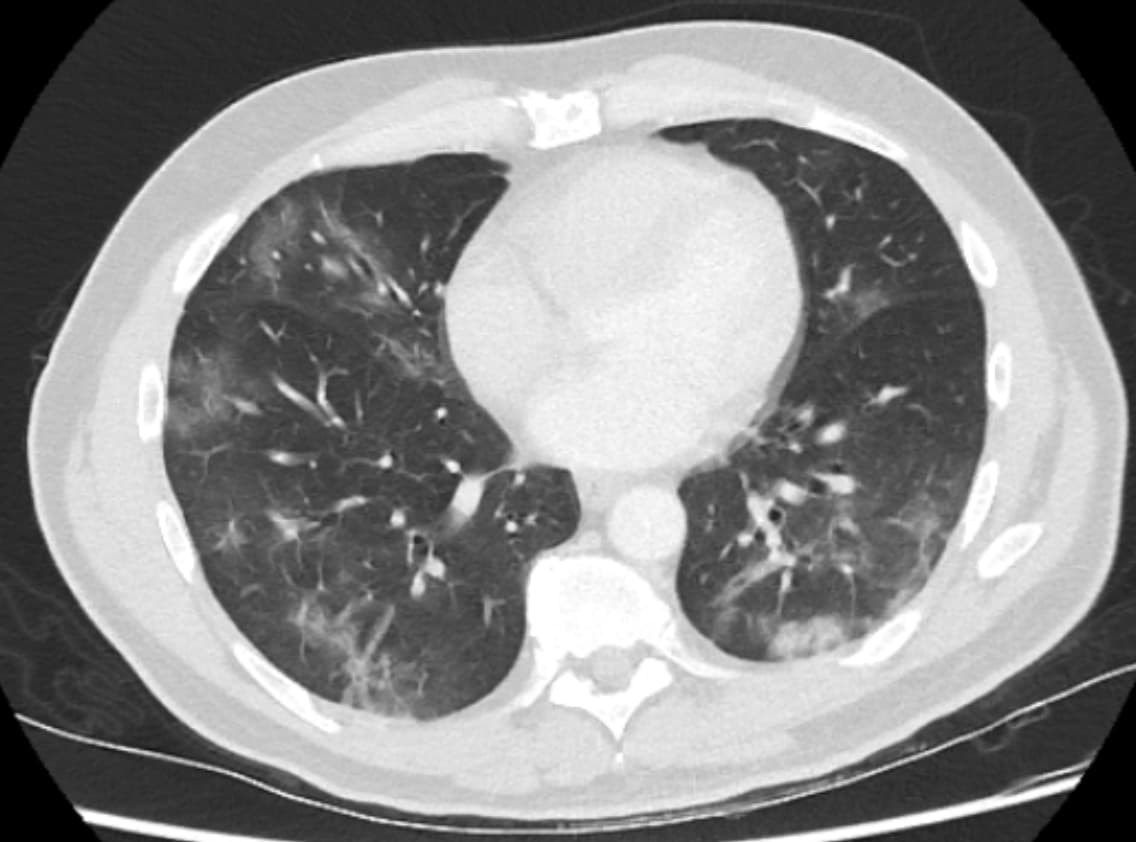

Obligatory features:

- Ground-glass opacities, with or without consolidations, in lung regions close to visceral pleural surfaces, including the fissures (subpleural sparing is allowed) AND

- Multifocal bilateral distribution

Confirmatory patterns:

- Ground-glass regions

- Unsharp demarcation, (half) rounded shape.

- Sharp demarcation, outlining the shape of multiple adjacent secondary.

- Pulmonary lobules.

- Crazy paving.

- Patterns compatible with organizing pneumonia.

- Thickened vessels within parenchymal abnormalities found in all confirmatory patterns.